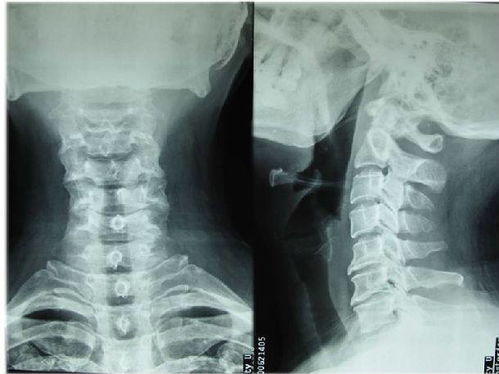

3.頸椎病人帶頸托3---6周,腰椎病人帶護(hù)腰帶3---6個月